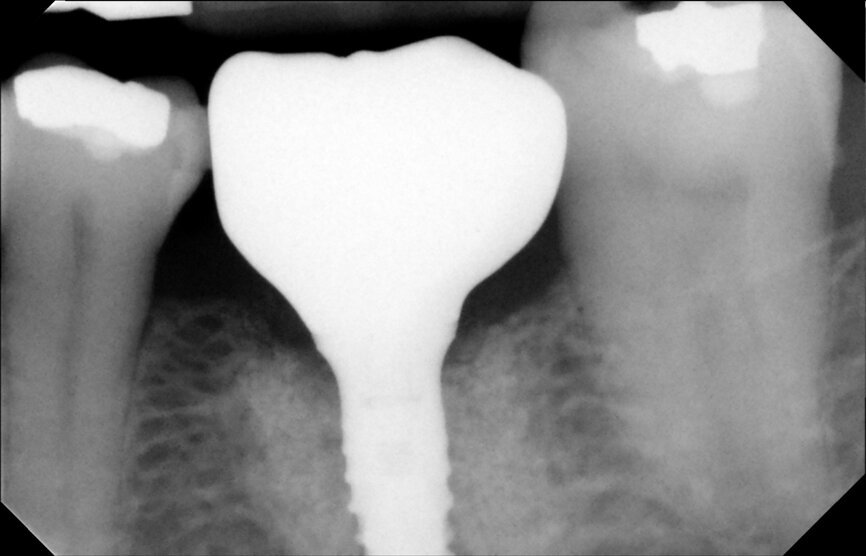

Fig. 17: Periapical radiograph after implant placement.

Fig. 18: Temporary crown.

It was possible to verify solid interradicular bone availability (Fig. 5), extending further the limits of the root apices and allowing for a centrally oriented osteotomy. The implant bed preparation started with the use of a needle drill at 800 rpm, followed by the ⌀ 2.2 mm and ⌀ 2.8 mm drills (Figs. 6–10). The implant was placed with the use of ratchet and torque control, reaching the desired final position at a 50 N cm torque value (Figs. 11–13). The socket was then augmented with bovine-derived bone substitute impregnated with advanced platelet-rich fibrin (A-PRF) and finalised with sutures to keep the A-PRF application immobile, and a 3 mm healing abutment was placed (Figs. 14–17).